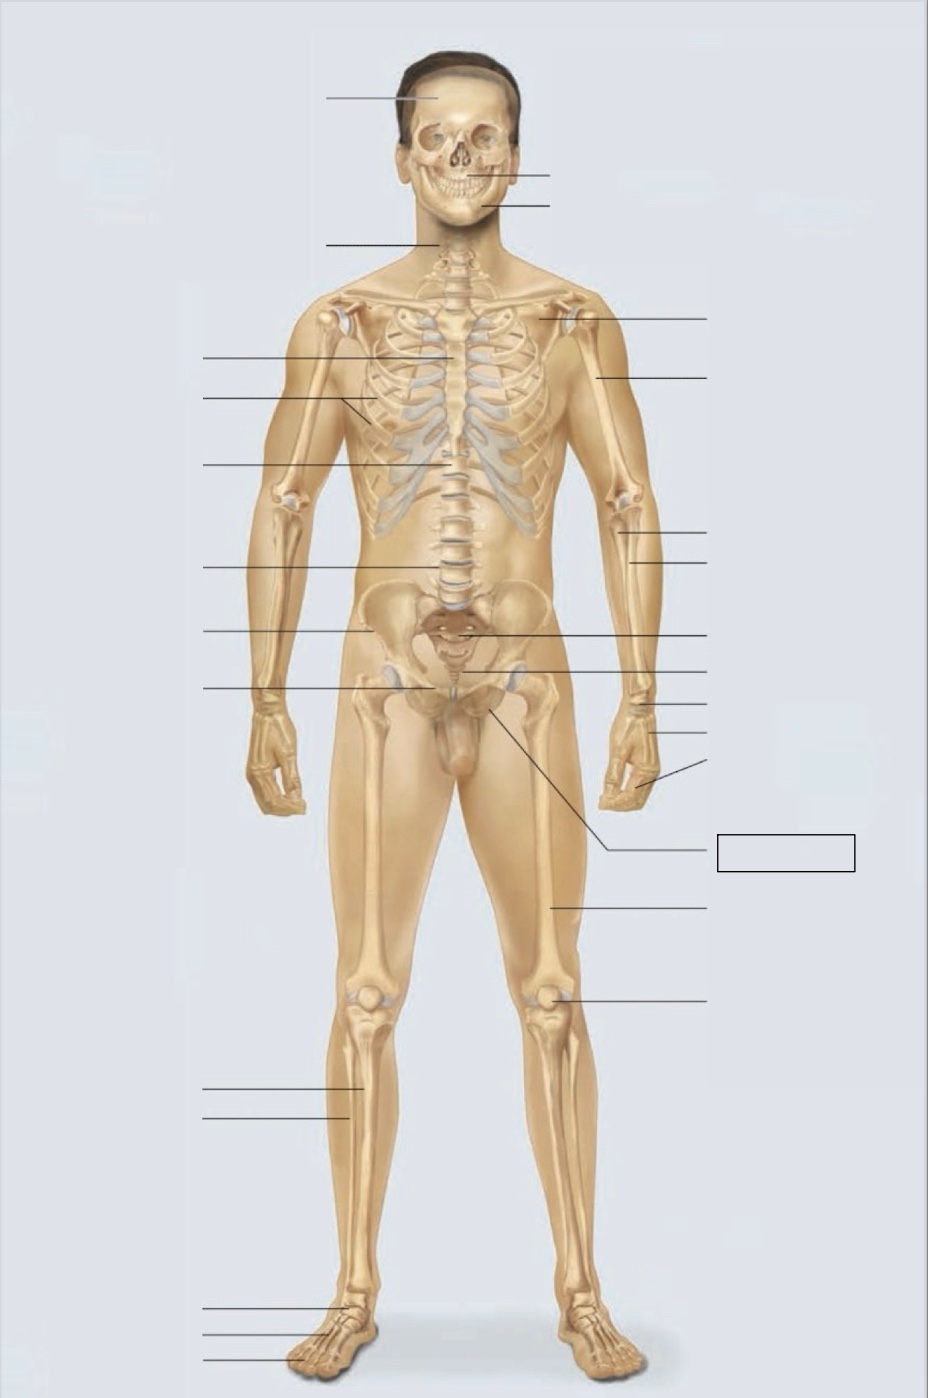

maxilla

mandible

scapula

humerus

ulna

radius

sacrum

coccyx

carpals

metacarpals

phalanges

ischium

femur

patella

phalanges

metatarsals

tarsals

fibula

tibia

pubis

ilium

lumbar vertebrae (L4)

thoracic vertebrae (T11)

ribs

sternum

cervical vertebrae

skull